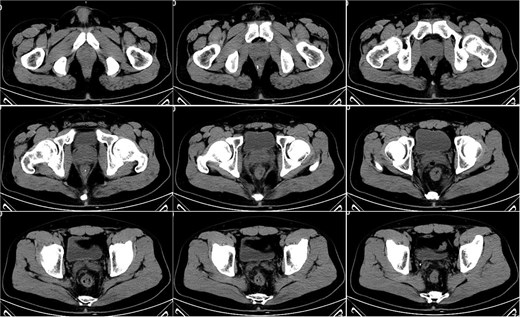

On postoperative Day 15, a complete blood count showed a white blood cell count of 9.12 × 109/l and a neutrophil percentage of 77.5%. Pelvic CT demonstrated rectal wall edema, anterior wall perforation, and partial absorption of the surrounding infection, indicating reduced infection severity compared to the previous scan on postoperative Day 10 (Fig. 3). Given the patient’s satisfactory response to antibiotic therapy and absence of ongoing infection signs, intravenous antibiotic treatment was discontinued.